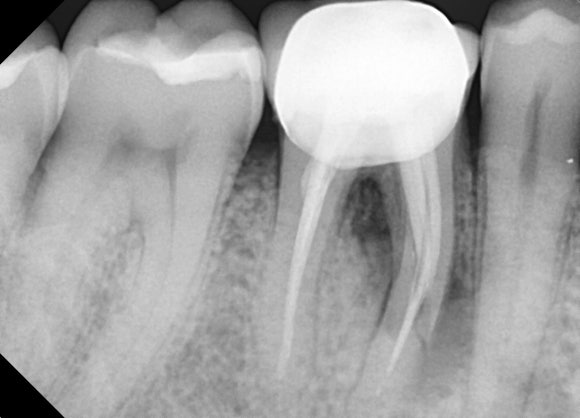

20250620

문제가 되는 뿌리 부분을

깨끗이 발거하였습니다.

다행히 남아있는 뿌리는 길이도 길고

잇몸뼈도 건강하여

남은 치아를 잘 지지해주리라 판단했습니다.